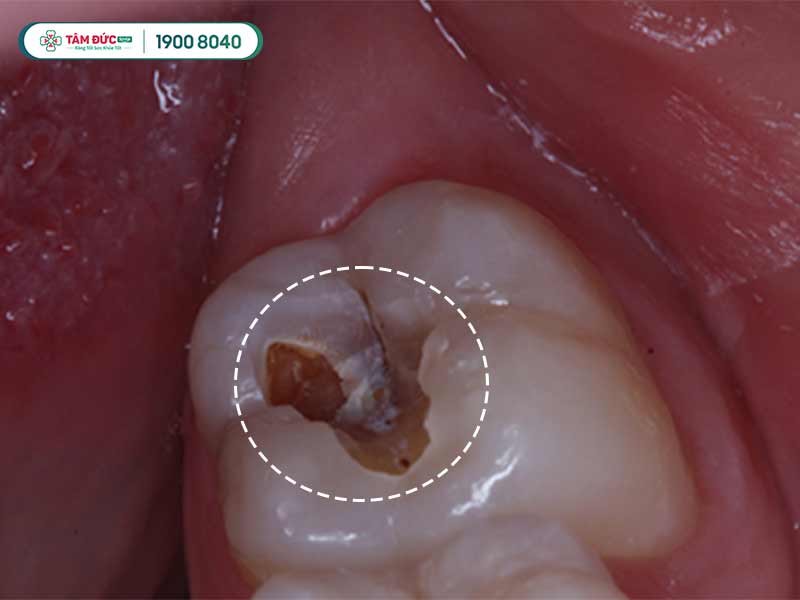

1.1.2. Sâu răng và nhiễm trùng

Do răng khôn mọc vị trí ở trong cùng nên rất khó để vệ sinh, thức ăn và vi khuẩn dễ dàng tích tụ. Sự tích tụ này lâu ngày sẽ gây ra sâu răng, nếu để lâu không chữa thì sẽ rất đau và nhiễm trùng có thể xảy ra.

Sâu răng khôn